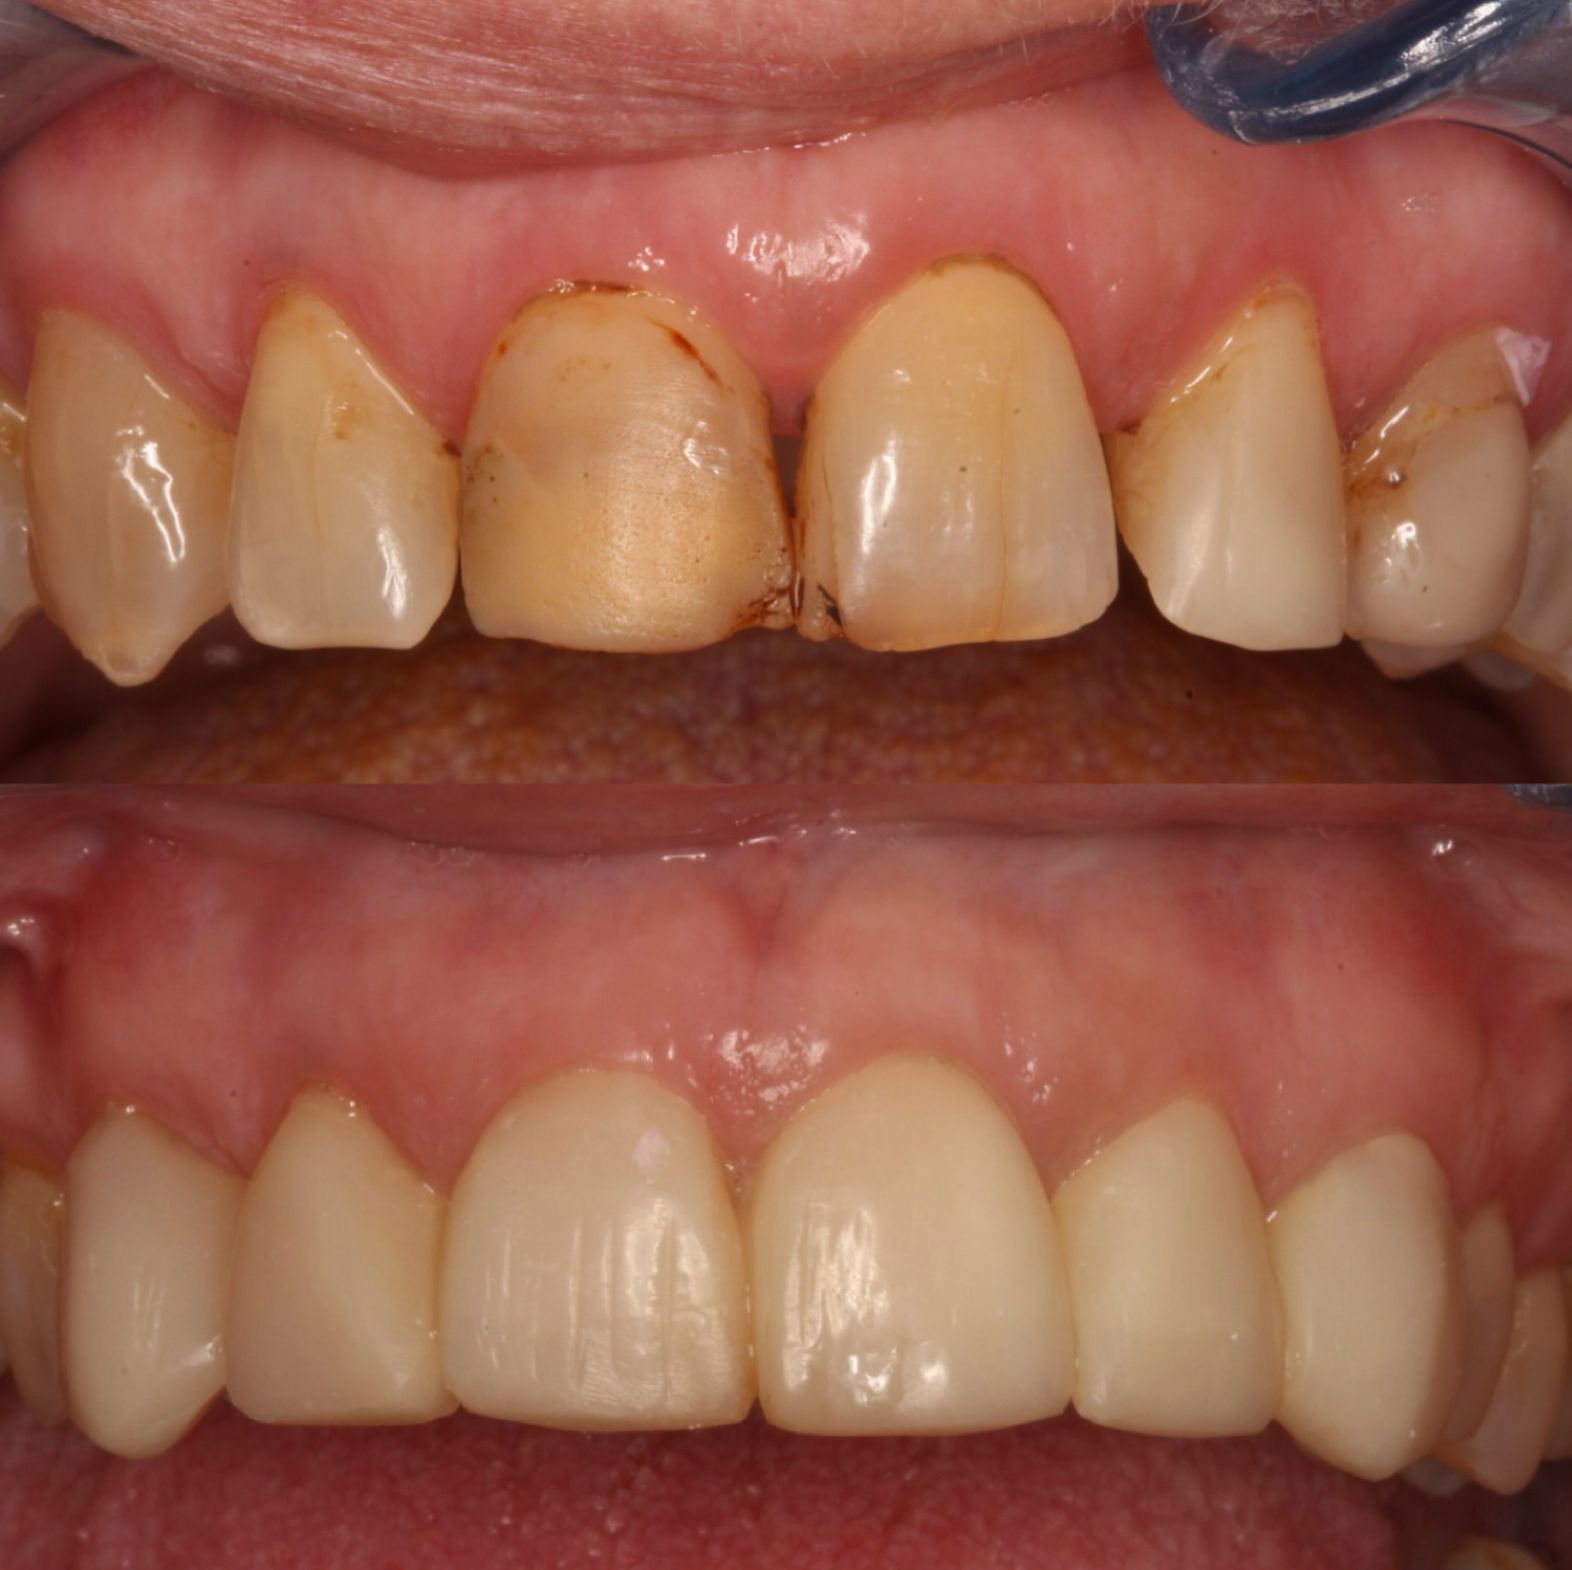

PRÓTESIS SOBRE IMPLANTES SUPERIOR E INFERIOR